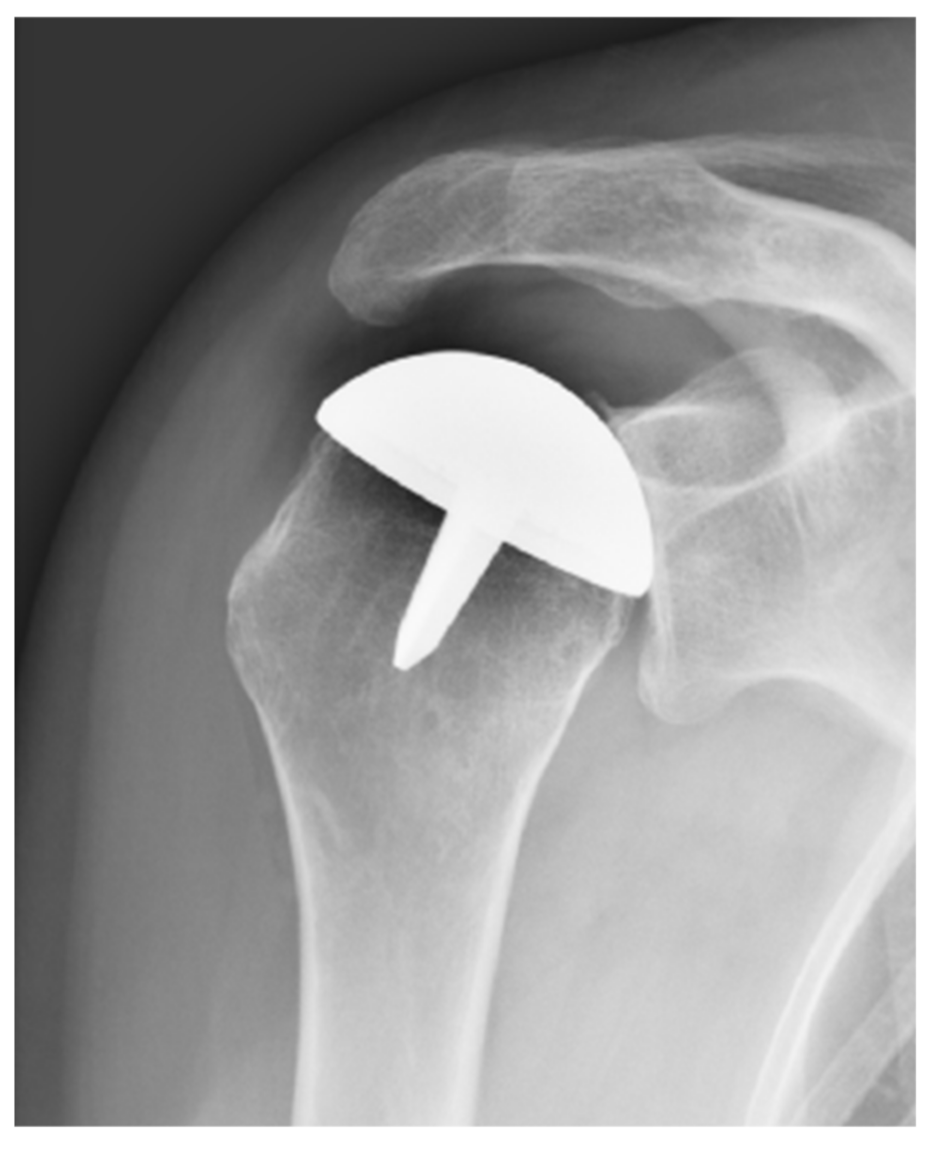

2.3. Hemiarthroplasty Group